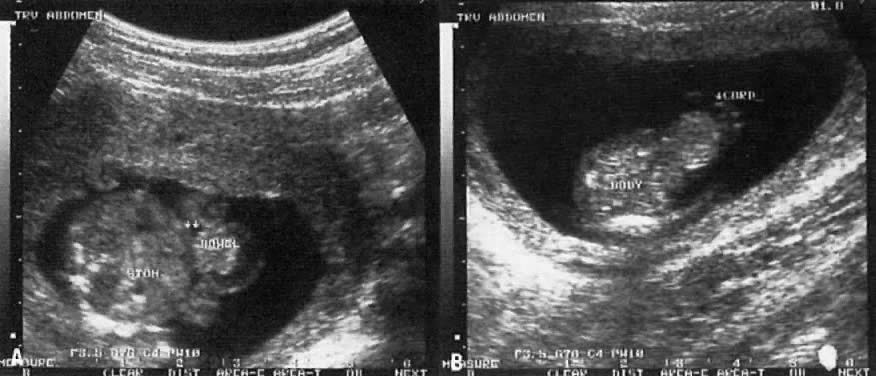

True ventral wall defects occur at a rate of 1:2500 births. Two main forms are described: omphalocele and gastroschisis. In omphalocele, the fetal gut (and sometimes the liver) is outside the abdomen but is covered by a sac-like cyst interface (Fig. 11). In gastroschisis, segments of intestine are noted in the peritoneal cavity without any sac-like cover. In contrast to omphalocele, the umbilical cord in gastroschisis is inserted into the abdominal wall (see Fig. 11). Gastroschisis is not associated with other fetal abnormalities, but a chromosomal abnormality may be found in approximately 50% of fetuses with omphalocele, particularly if fetal liver is not part of the hernia.36, 37 Other anomalies involving the cardiac, skeletal, renal, and central nervous systems may also be present. The Beckwith-Weidman syndrome of organomegaly and hypoglycemia has been described in association with omphalocele.

Fig. 11. A. Cross-section echogram of a fetus with an omphalocele. Note herniation of bowel covered by a fluid interface and sac wall. B. In another view, the umbilical cord (CORD) is seen tot enter into the sac, which is characteristic of an omphalocele.

In the presence of a ventral wall defect, the mode of delivery (vaginal delivery vs cesarean section) remains controversial.38, 39 Vaginal delivery appears safe, however, when the hernia is small and the liver is not herniated.